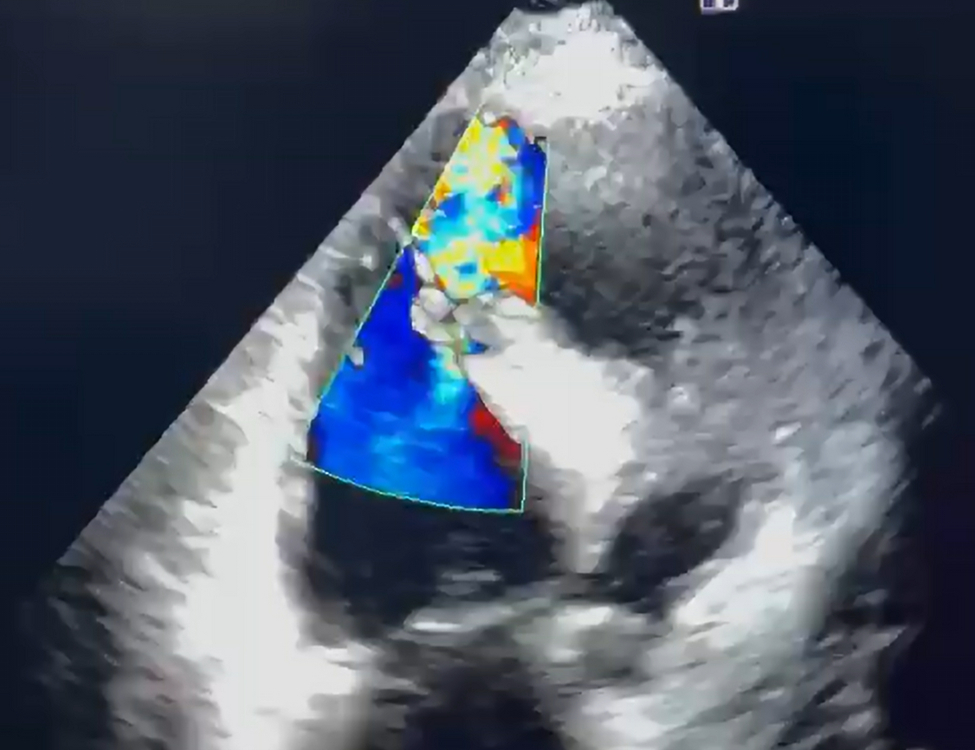

Case Summary: This case report presents the case of a 70-year-old female who presented to a community hospital in Pakistan in January 2024 with chest pain and progressive dyspnea that started seven days after an MI diagnosis. Her echocardiogram revealed an apical VSD, while coronary angiography confirmed dual-vessel coronary artery disease. Subsequently, she underwent elective subacute surgical repair of a 3x3 cm apical VSD along with coronary artery bypass grafting (CABG) and intra-aortic balloon pump placement. Postoperatively, she developed a ventricular thrombus, which was managed with anticoagulation. Follow-up echocardiography demonstrated marked clinical improvement.